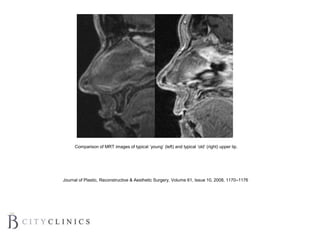

Comparison of MRT images of typical ‘young’ (left) and typical ‘old’ (right) upper lip.

Journal of Plastic, Reconstructive & Aesthetic Surgery, Volume 61, Issue 10, 2008, 1170–1176